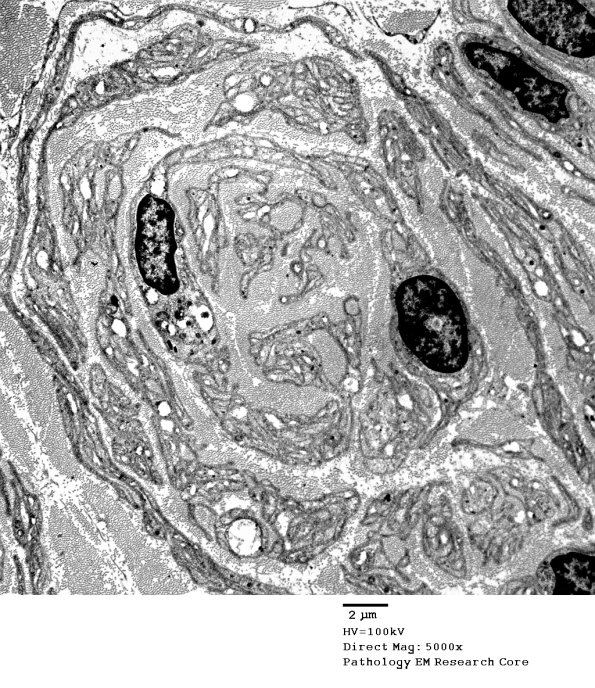

1C15A,B The individual pseudo-onion bulbs appear uniform. (electron micrographs)